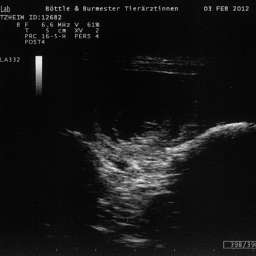

3.2.2012, 32.Tag: Der Ultraschalltermin ist vollbracht: Juhu, wir werden Eltern!!!

Aus Herzklopfen wurde Herzrasen und dann endlich, kurz vor der Herztablette, zeigte uns der Ultraschall 5 KLEINE WUNDER, gesunde Fruchthüllen, mit lebendigem Innenleben und pochendem Herzen. (...passte sehr gut zu unseren...)Wieviele es letztendlich werden, bleibt eine riesige Überraschung.

Bitteschön, ein kleines Filmchen mit dem Titel: "5 auf einen Streich, oder wie es in den Bauch hineinschallt, schallt es auch wieder hinaus."

4.2.2012, 33.Tag: Hier sind also die Fotos der kleinen Flauschmonster in ihren Höhlen.

Sucht Euch doch schon mal einen aus: